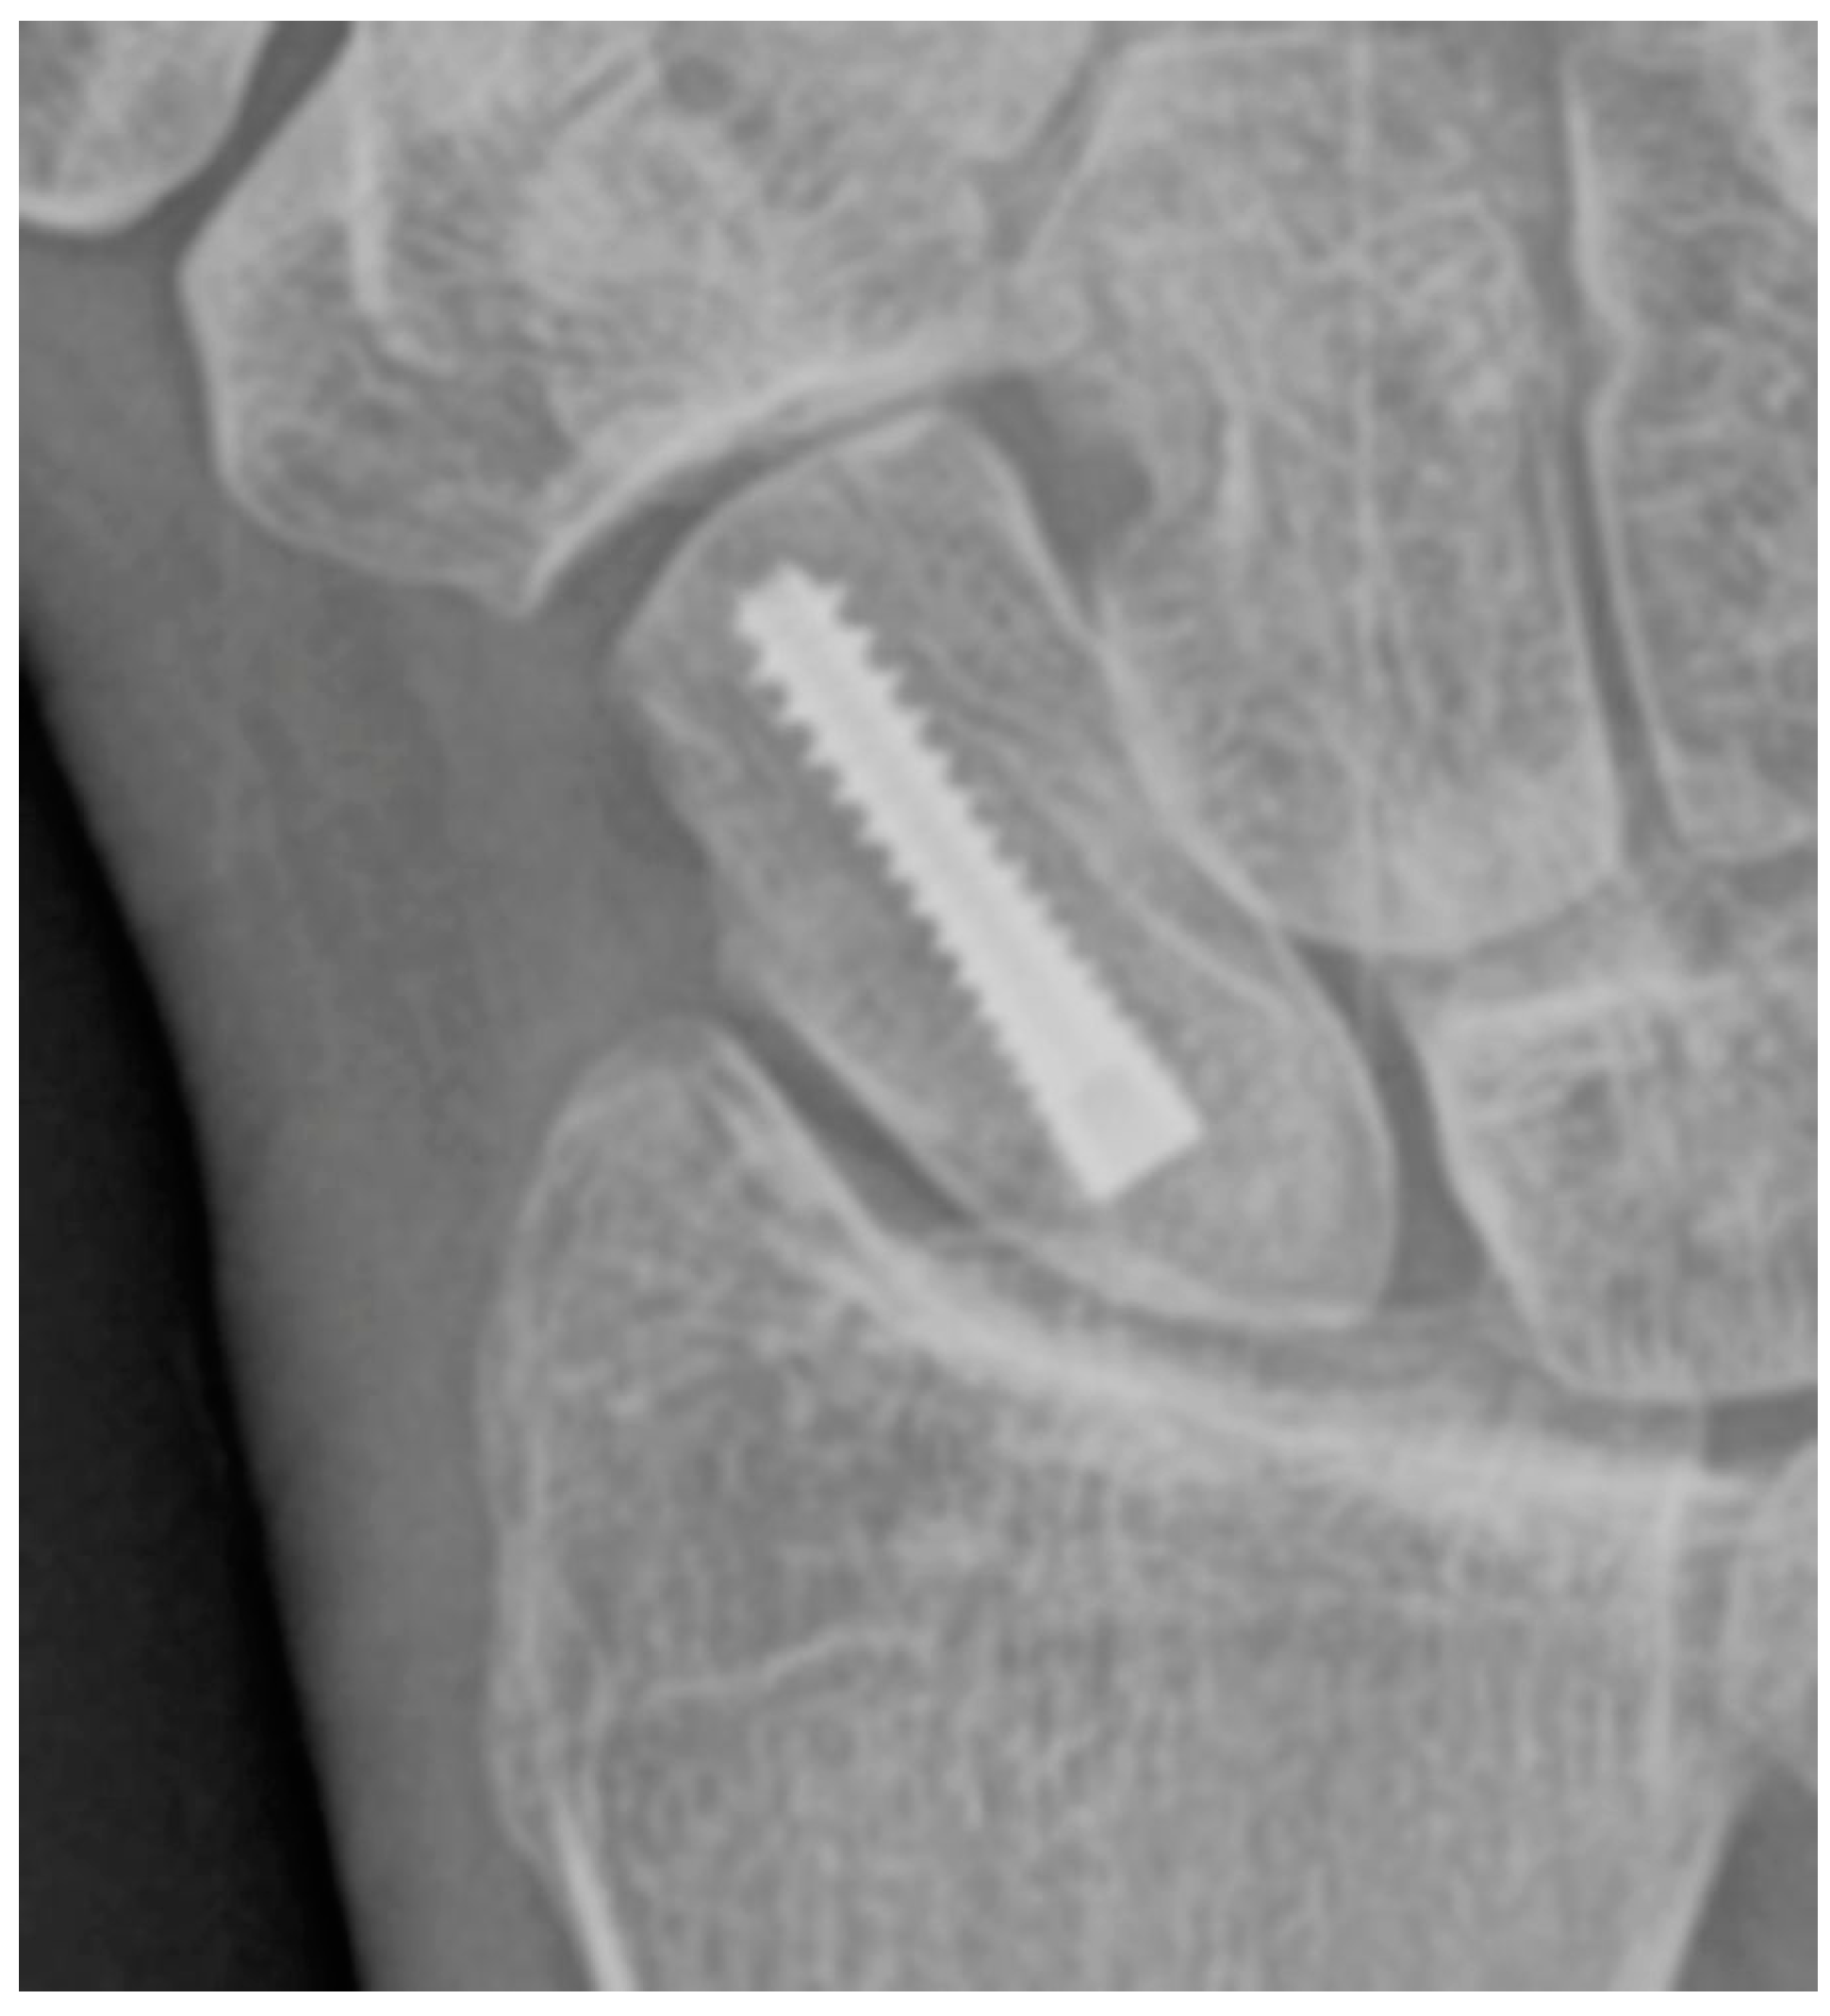

Figure 8. PA radiograph showing surgical fixation of a scaphoid fracture utilizing a variably threaded headless compression screw, allowing it to be countersunk beneath the articular surface, removing the need for retrieval after the fracture has healed. In this case, the screw has been introduced via a dorsal approach, advanced from proximal to distal.

Conservative management of scaphoid fractures consists of cast immobilization across the wrist including the first metacarpophalangeal joint. This is the most widely used management strategy for scaphoid fractures, particularly when the fracture is stable [2,5,18]. Low rates of morbidity and long-term disability are advantages of a conservative approach; however, this may require prolonged time to resume work and daily activities of living compared to surgical fixation. The surgical approach involves minimally invasive screw fixation using a compression (e.g. Herbert or Accutrak) screw to allow early mobilization, improving return to activity time over casting. The surgical approach utilizes threaded headless screws (Figure 8), allowing them to be countersunk beneath the articular surface and eliminating the need for removal after fracture healing [17]. Variable threading of the fixation screw promotes compression at the fracture site, facilitating healing. Percutaneous screw fixation is contradicted in displaced scaphoid fractures or with nonunion because the fracture may become displaced during the procedure, requiring a subsequent open reduction. A supplementary option for scaphoid fractures with nonunion or sclerosis and/or cystic change is a vascularized bone graft. In these cases, a bleeding surface is reestablished at the fracture site for the bone graft containing a vascular pedicle to be incorporated into. The vascular pedicle is typically salvaged from the distal radius (Figure 9A) and inserted into the revitalized fracture gap to reestablish blood flow to the proximal pole (Figure 9B). The vascular pedicle is anastomosed with the radial artery [19].